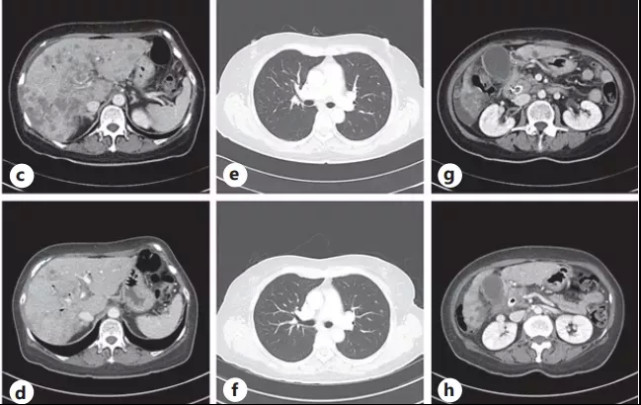

图2. (a)脂质体伊立替康治疗前,胰腺癌的原发灶和多发性肝转移。(b)脂质体伊立替康五个月后,原发灶体积缩小,肝转移消失

停药两个月后,患者病情加重,确诊为广泛肝转移(图2 c-e),经多方考量,决定重新应用NAPOLI方案。治疗再次有效,共持续了7个月(2020年7月–2021年1月),CT 显示胰腺肿物减小,转移病灶均有所改善。

图2.(c-e)在重新使用脂质体伊立替康之前,广泛的多发性肝转移、腹水、原发肿块的大小增加和肺转移。(f-h)再次使用脂质体伊立替康后6周,改善多器官转移并减少原发病灶。